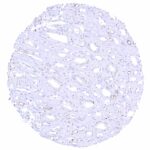

| Genitourinary | Kidney | A distinct CD70 staining of the luminal surface membrane can be seen in individual tubuli and at the parietal layer of the Bowman capsule. It is possible, that these stainings only (or preferably) occur in case of tissue damage. |